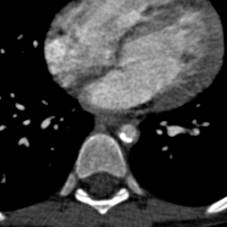

Компьютерная

томография: гипоплазия (тубулярное сужение от уровня перешейка до диафрагмы)

нисходящей грудной аорты с максимальным сужением до 6 мм в средней трети, кальцинатами стенки в этой

области.(рисунок 1)

А. В.

Рисунок 1. КТ-АГ аорты

при гипоплазии нисходящей грудной аорты

А. 3D реконструкция В. Аксиальный срез с участком кальциноза

аорты